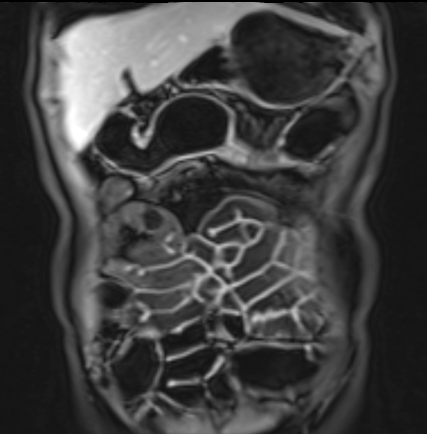

Bệnh nhân nữ 48 tuổi, đang điều trị bằng thuốc kháng TNF, được chỉ định nội soi đại tràng.

Phát hiện hẹp lòng ruột ở đại tràng sigma, không thể vượt qua được khi nội soi.

MR-enterography được thực hiện để đánh giá mức độ lan rộng của chỗ hẹp.

Ruột non bình thường, nhưng ghi nhận các đoạn hẹp ở đại tràng xuống và đại tràng ngang.

Cả hai đoạn hẹp đều có thành ruột dày đến 8 mm và ngấm thuốc rõ rệt theo kiểu niêm mạc ở đại tràng xuống và kiểu phân lớp ở đại tràng ngang.

Giãn ruột trước chỗ hẹp được ghi nhận ở cả hai đoạn.

Do các chỗ hẹp này không hiện diện khi nội soi đại tràng trước khi điều trị kháng TNF, nhiều khả năng chúng đã hình thành trong quá trình điều trị.

Do đó, quyết định phẫu thuật cắt đại tràng gần toàn bộ với miệng nối hồi-sigma đã được đưa ra.